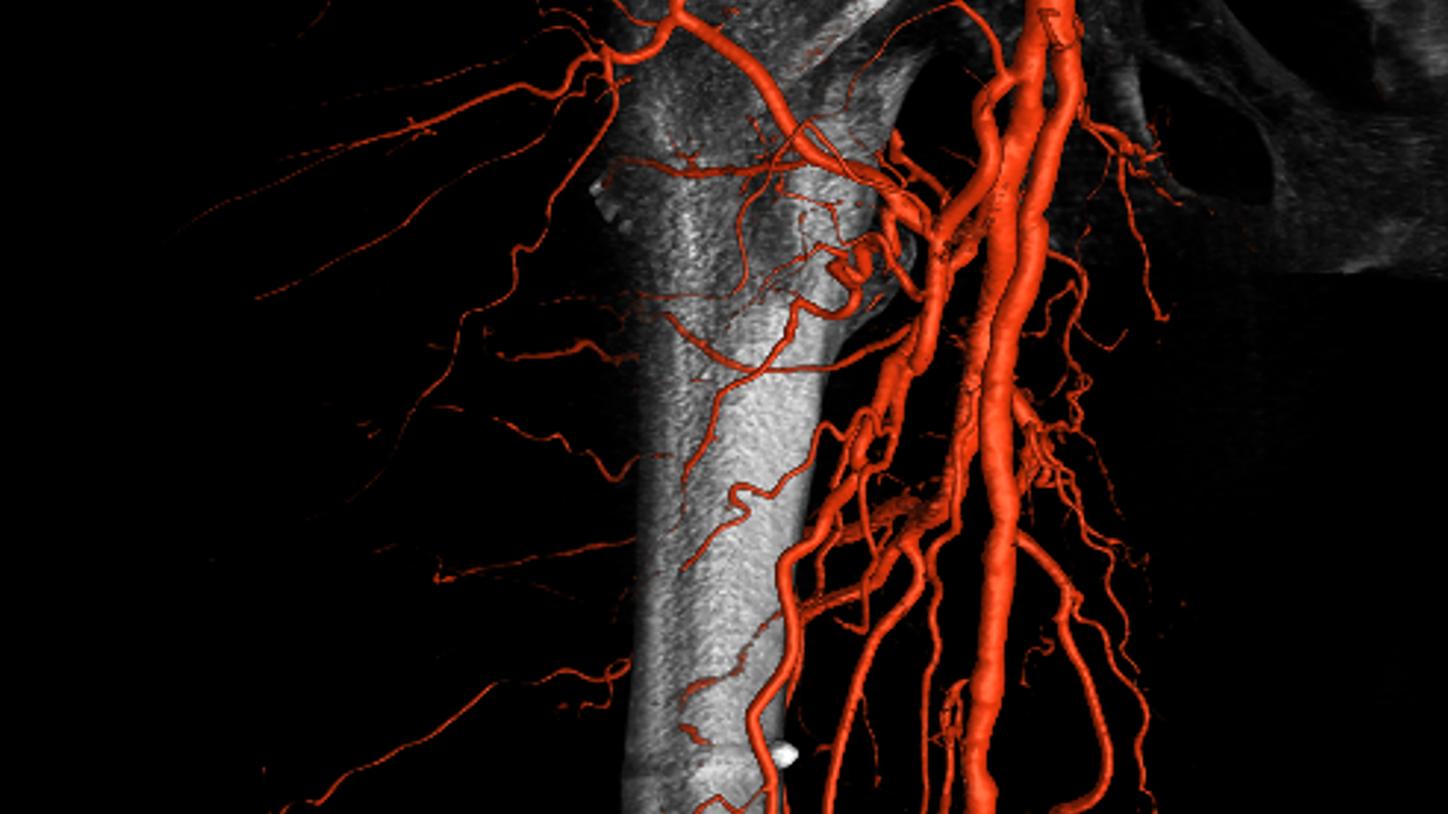

Simple and fast 3D imaging, everywhere

Generate 3D acquisitions with excellent spatial and soft tissue resolution whatever your clinical case is. With up to 95°/s rotation speed, ARTIS icono systems can acquire syngo DynaCT images in just 2.5 seconds with fewer motion artifacts and less use of contrast media.3 Simple and fast 3D imaging from head to toe with 200° rotation range gives you confidence in procedure planning.

Precise system movements

Precision is key to improve the workflow in complex procedures. The reuse of vessel maps for DSA and 3D Roadmap even after C-arm and table movements speeds up the intervention and reduces dose and use of contrast media. ARTIS icono supports this with a (re)positioning accuracy of better than 0.5 mm.